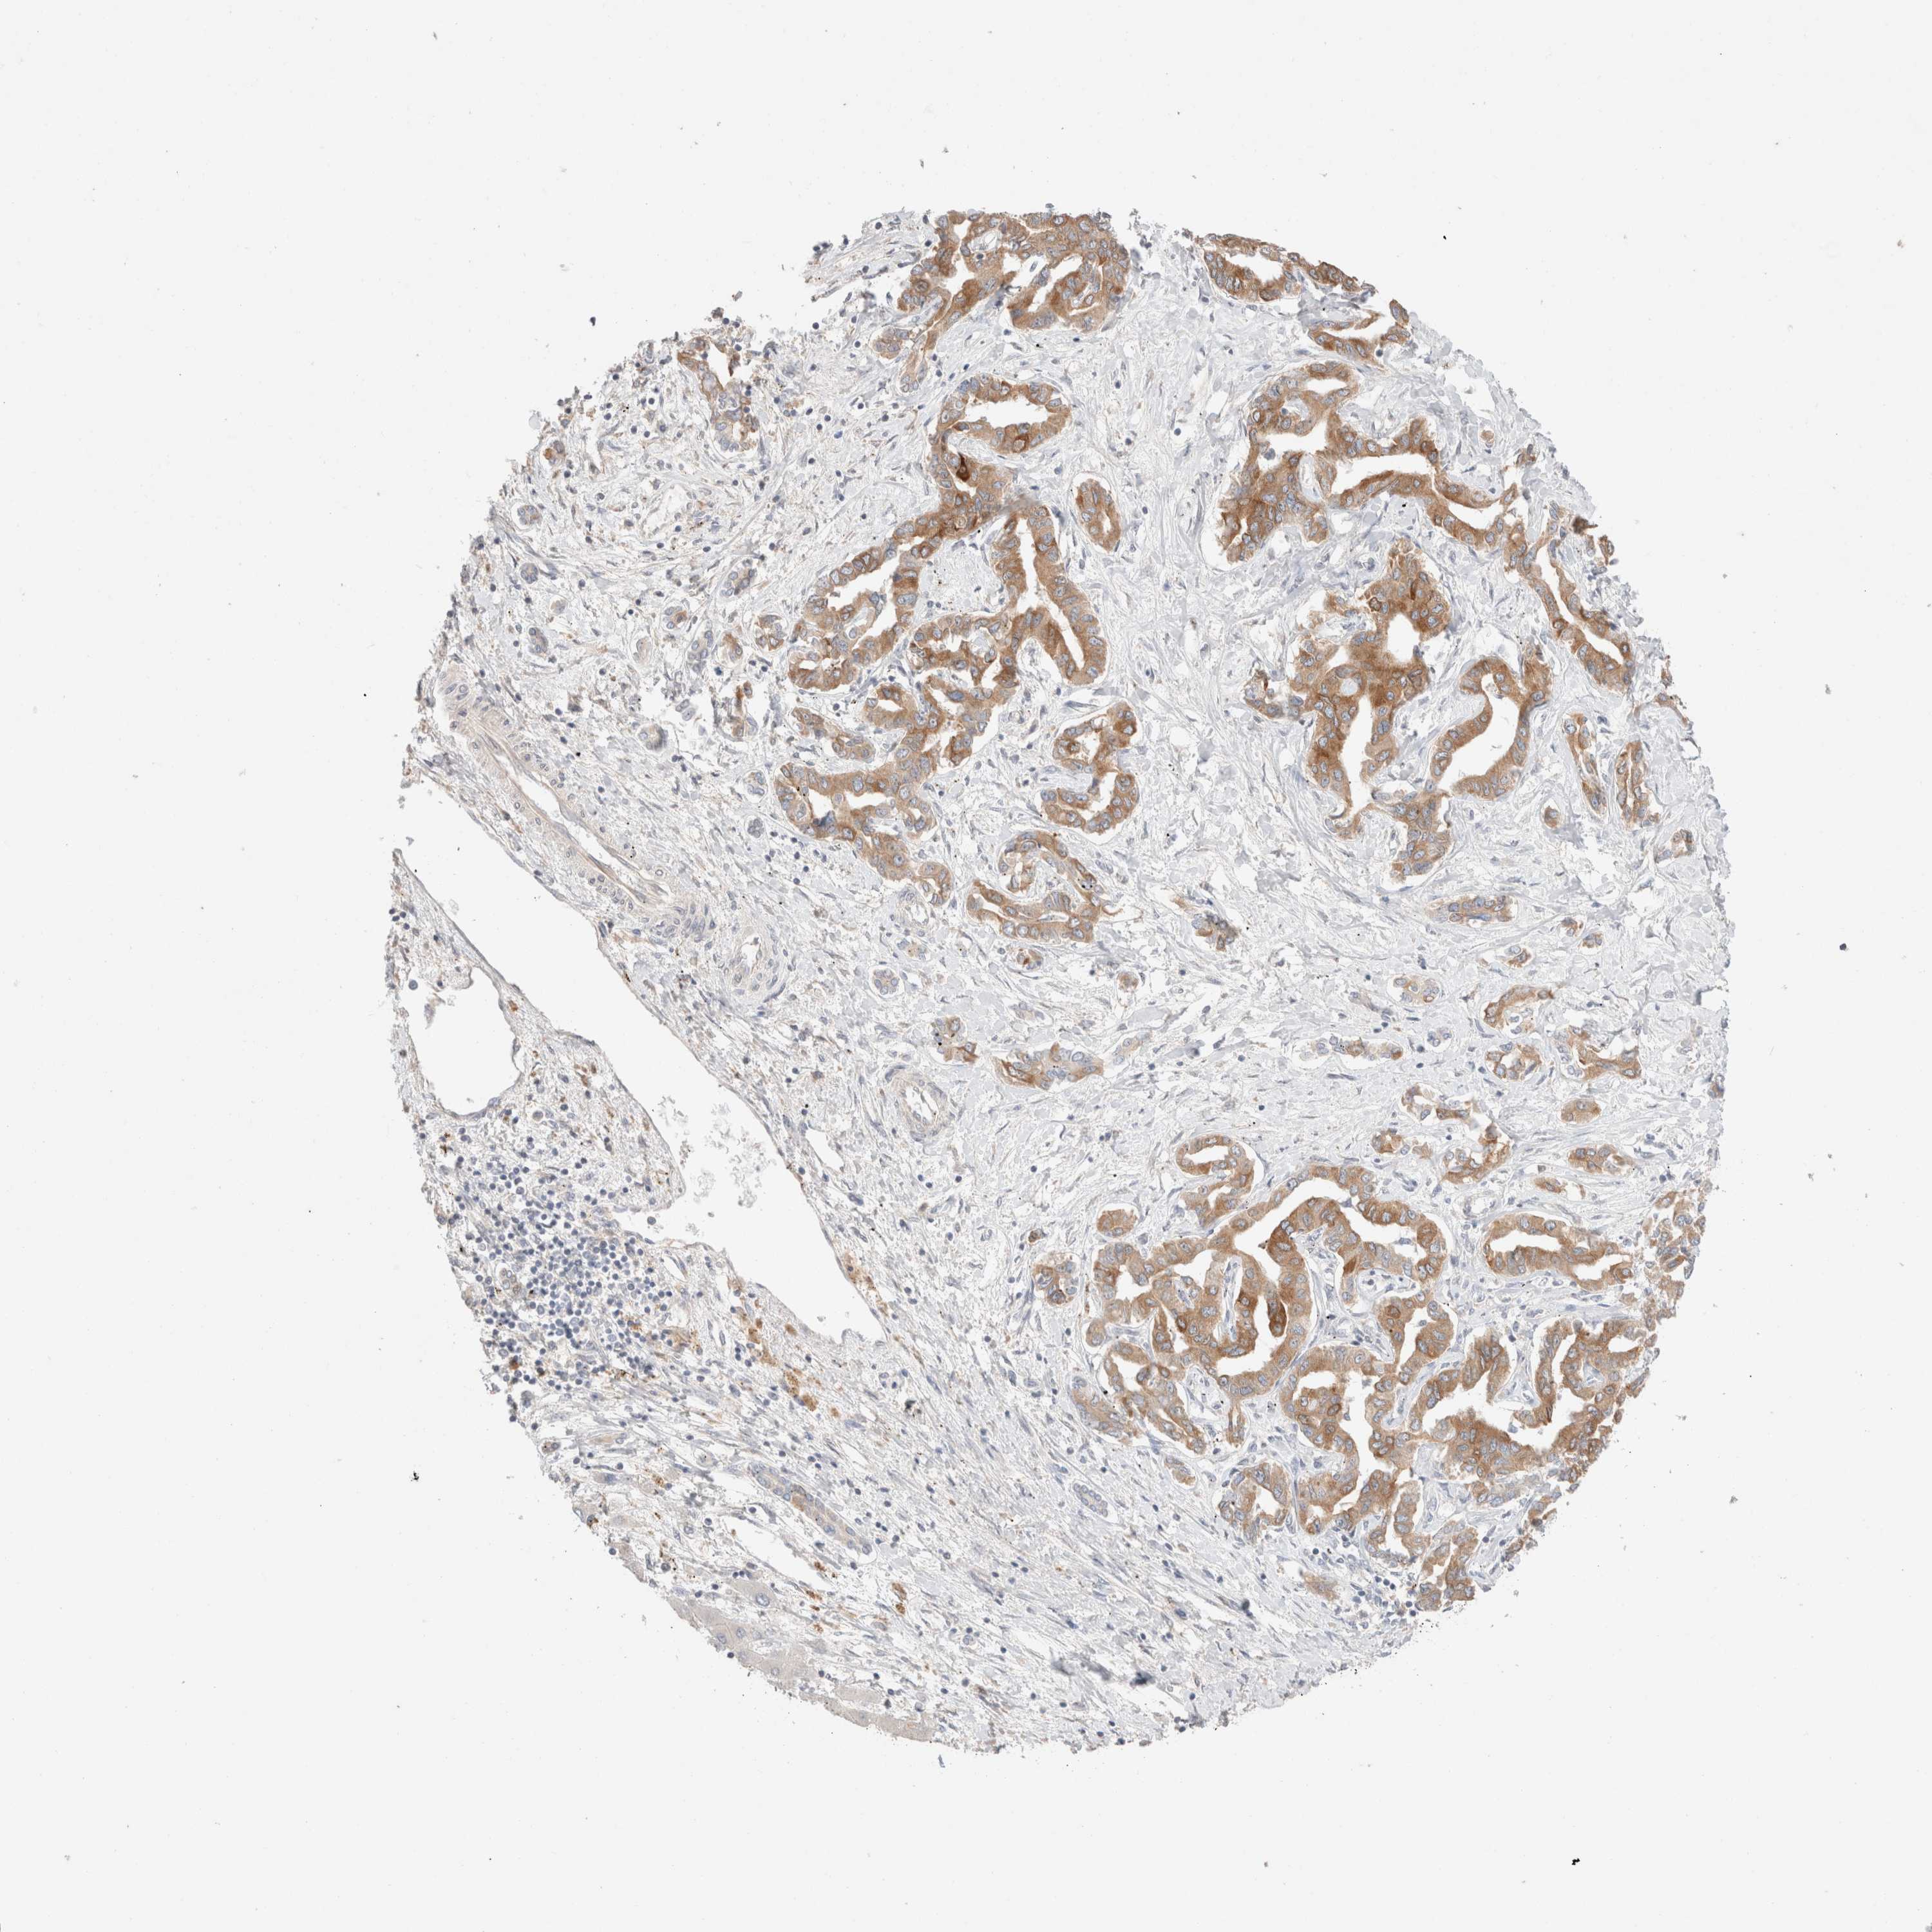

LIVER CANCER - Protein expressioni

A mouse-over function shows sample information and annotation data. Click on an image to view it in a full screen mode. Samples can be filtered based on level of antibody staining by selecting one or several of the following categories: high, medium, low and not detected. The assay and annotation is described here.

Note that samples used for immunohistochemistry by the Human Protein Atlas do not correspond to samples in the TCGA dataset.

Antibody stainingi

Antibody staining in the annotated cell types in the current human tissue is reported as not detected, low, medium, or high, based on conventional immunohistochemistry profiling in selected tissues. This score is based on the combination of the staining intensity and fraction of stained cells.

Each image is clickable and will lead to virtual microscopy that enables deeper exploration of all samples and also displays staining intensity scores, fraction scores and subcellular localization as well as patient and tissue information for each sample.

Antibody HPA024204

Staining

High

Medium

Low

Not detected

Intensity

Strong

Moderate

Weak

Negative

Quantity

>75%

75%-25%

<25%

None

Location

Nuclear

Cytoplasmic/membranous

Cytoplasmic/membranous,nuclear

Cholangiocarcinoma

Carcinoma, Hepatocellular, NOS